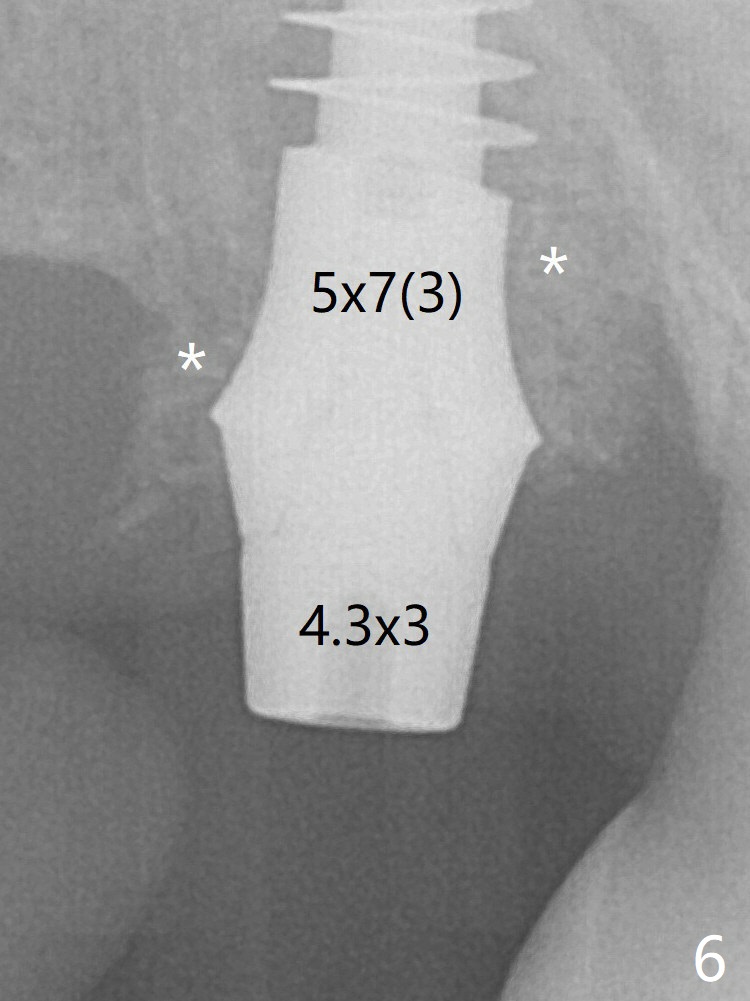

Trajectory is found to be off when 5x9 mm dummy FC implant is placed with stability (Fig.5 (*: defect)). The final implant, Magicore (5x7(3)mm, >29 Ncm), appears to be placed too deep for restoration (Fig.6,7); a screw retained crown may be a solution. PRF membrane and Vanilla (allograft) are used for sinus lift (no sinus membrane perforation). Following Vanilla graft in the socket gap (Fig.6 *), another piece of PRF membrane is used to cover socket opening. The membrane is fixed in place with suture and periodontal dressing. When a FC implant is placed too deep, a pair abutment with longer cuff will solve the problem. With Magicore, the diameter of abutment is unable to change. The implant seems to have osteointegrated 3.5 months postop (Fig.8). After change to 4.3x5 mm solid abutment and mesial surface adjustment, impression is taken for early loading because of removal of #14 implant. In fact the patient is satisfied with mastication improvement at #2 later on.